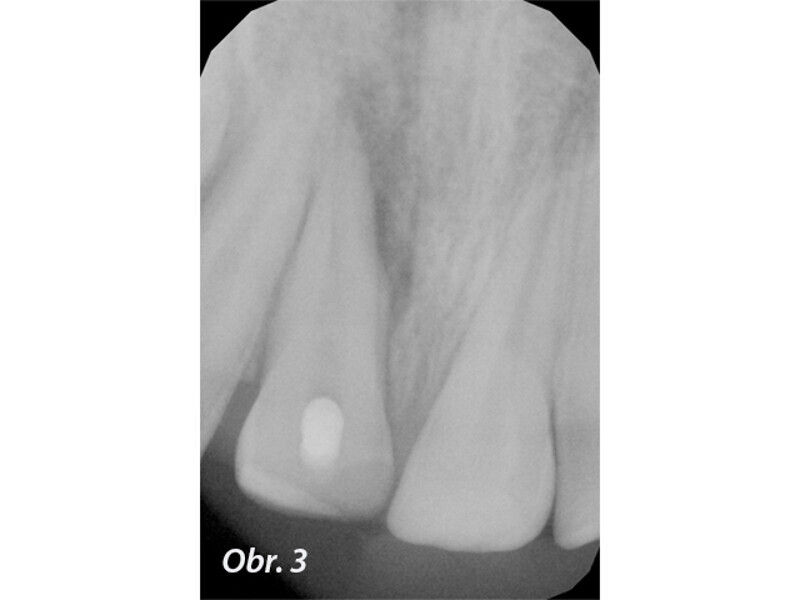

Endodontické ošetření horního středního řezáku s atypickou anatomií